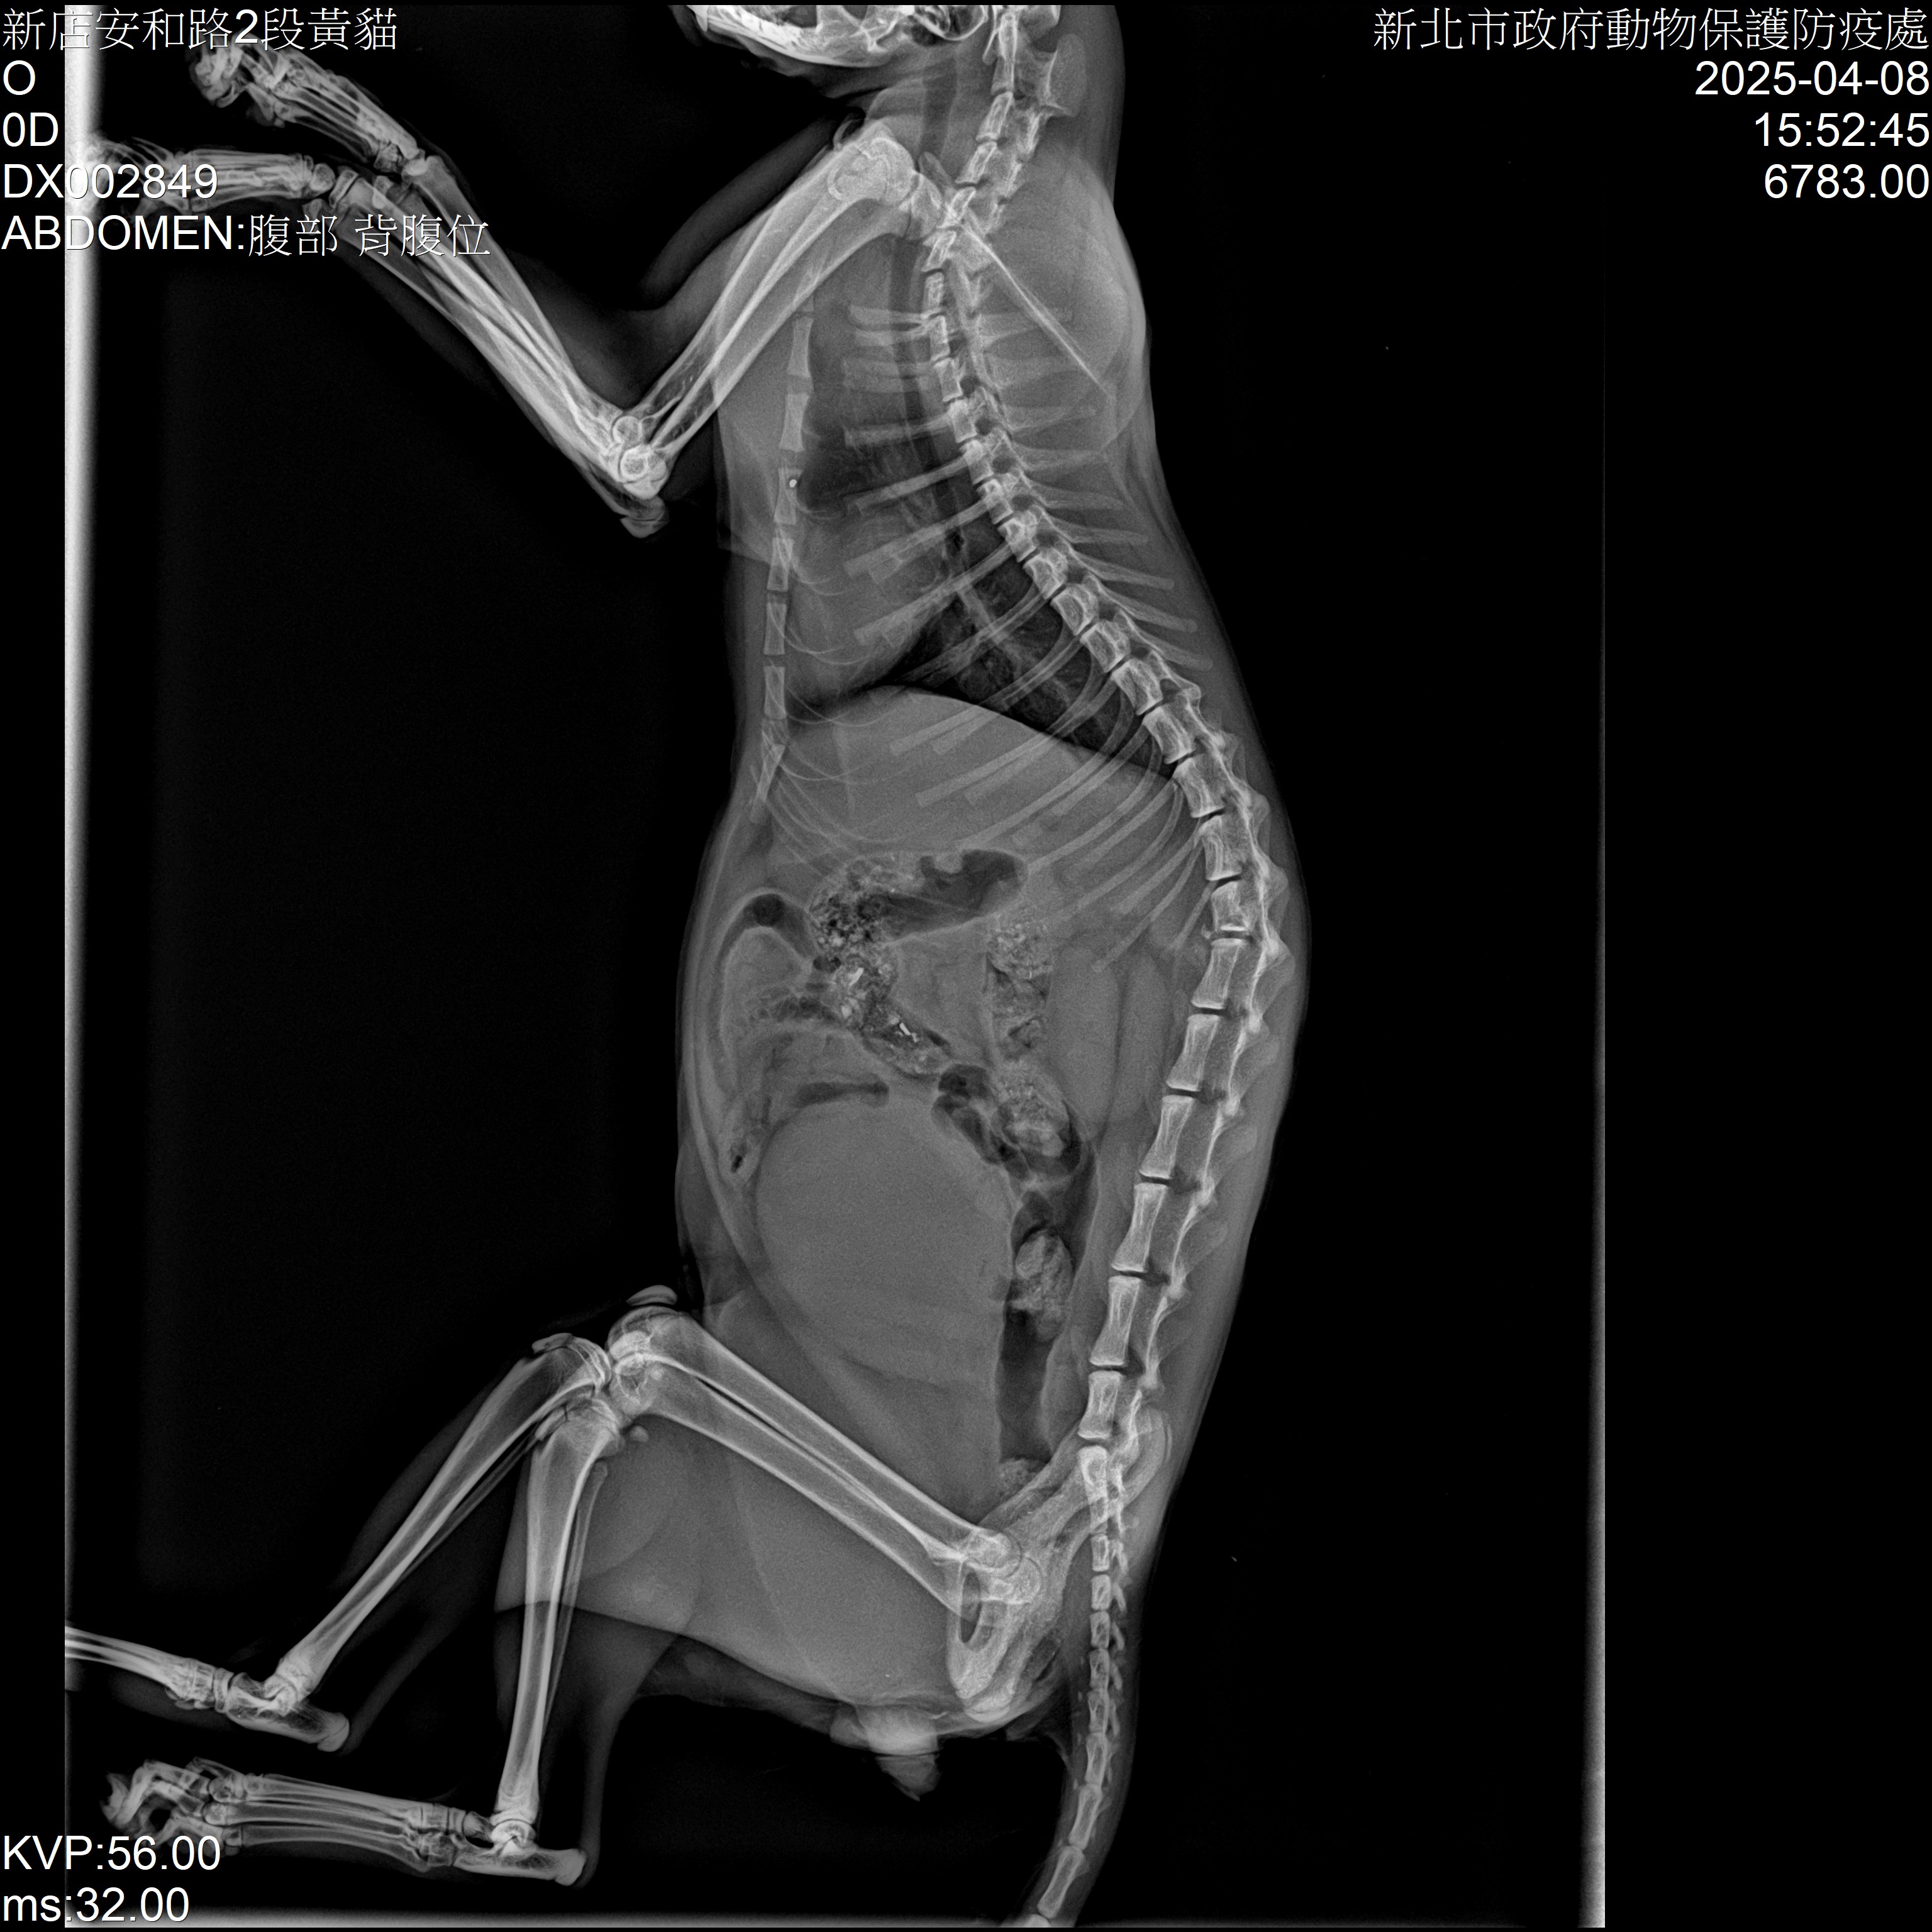

小橘貓經新店動物之家的獸醫師李建沛診斷,X光片顯示小橘貓腰椎遭受壓迫,導致後肢癱瘓,無法站立行走。然而令人欣慰的是,經細心觀察,小橘貓仍能自行排便與排尿,堪稱不幸中的大幸。雖然小橘貓無法行走,但其生命力仍十分頑強。毛寶貝醫療中心為牠安排了初步的穩定治療,包括消炎止痛、營養補給以及保持膀胱功能監控。醫療團隊每日協助牠翻身,防止壓瘡產生,並進行復健性的輕柔按摩,促進血液循環,維持肌肉張力。同時,也進一步評估牠的生活品質與照護可能性。所幸小橘貓雖後肢癱瘓,但意識清楚、食慾正常,且能自行排便尿,代表其神經系統雖受損仍保有部分功能。這樣的狀況讓動保處決定不輕言放棄,持續觀察並配合後續復健計畫。